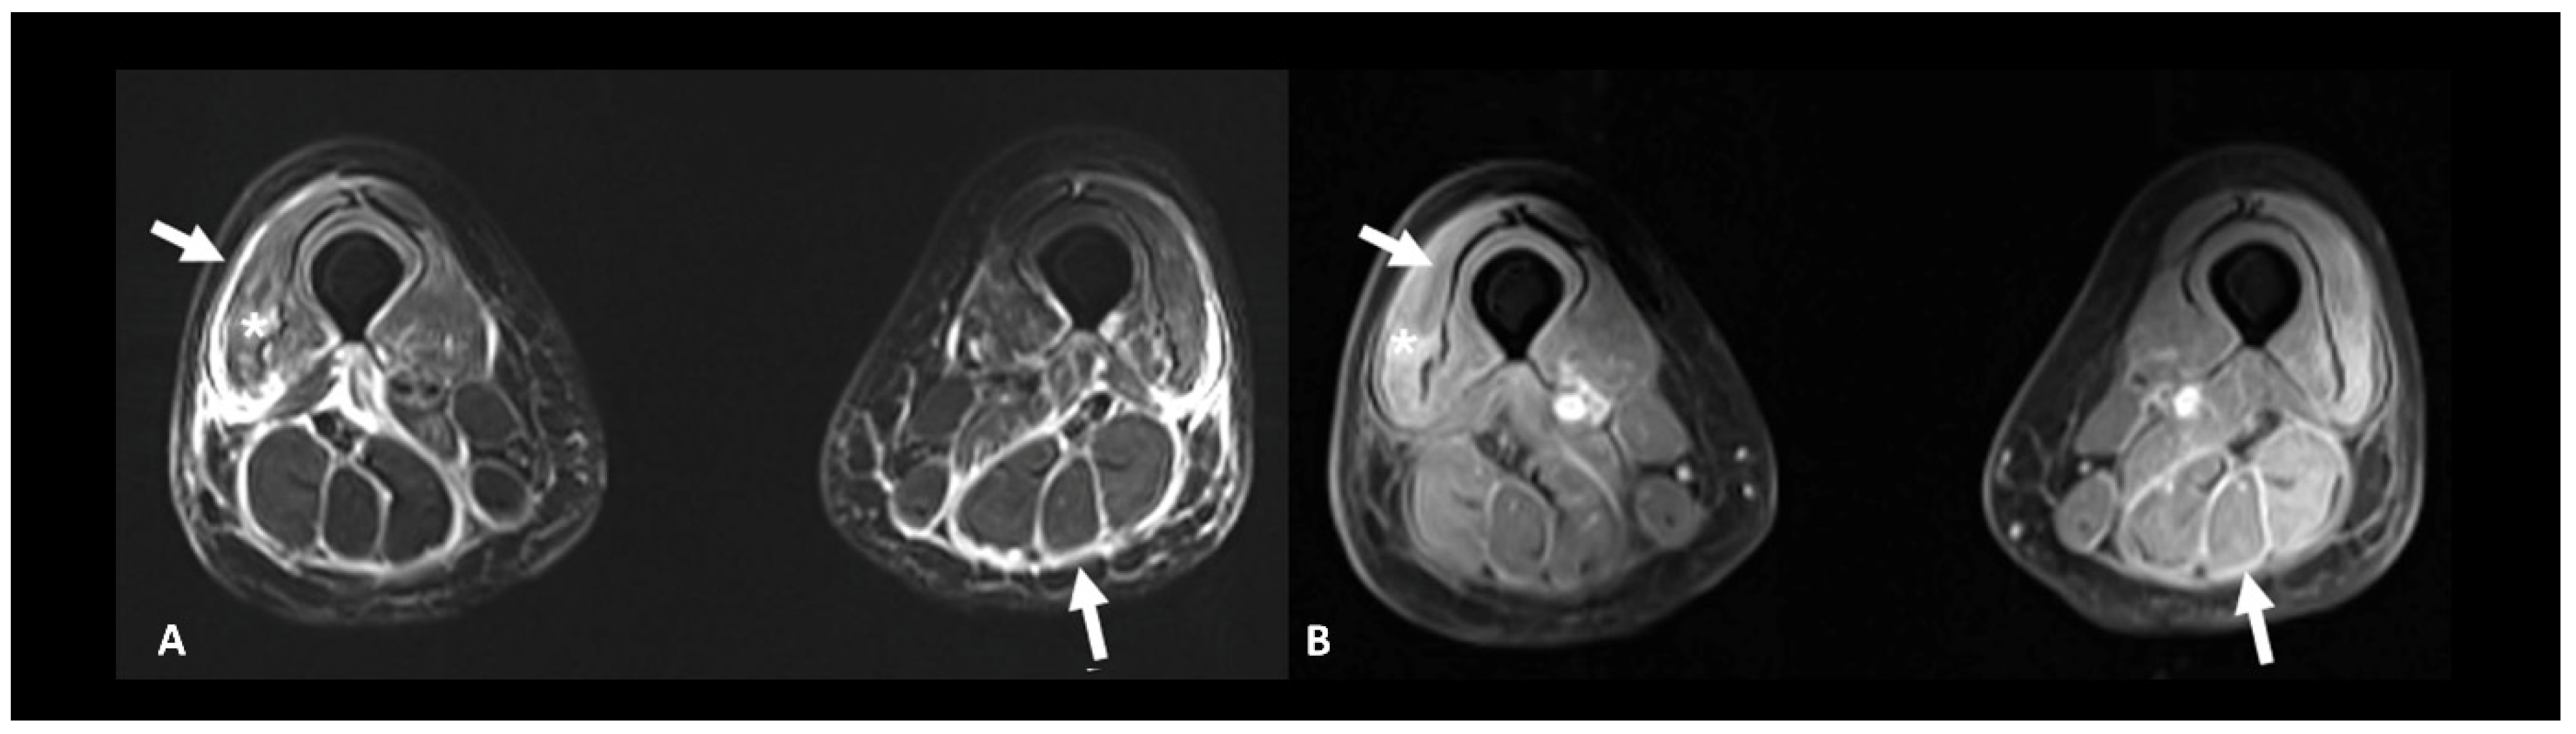

2.6. Ir-Rheumatological and Musculoskeletal Adverse Events

- Ponce, A.; Frade-Sosa, B.; Sarmiento-Monroy, J.C.; Sapena, N.; Ramírez, J.; Azuaga, A.B.; Morlà, R.; Ruiz-Esquide, V.; Cañete, J.D.; Sanmartí, R.; et al. Imaging Findings in Patients with Immune Checkpoint Inhibitor-Induced Arthritis. Diagnostics 2022, 12, 1961. [Google Scholar] [CrossRef]